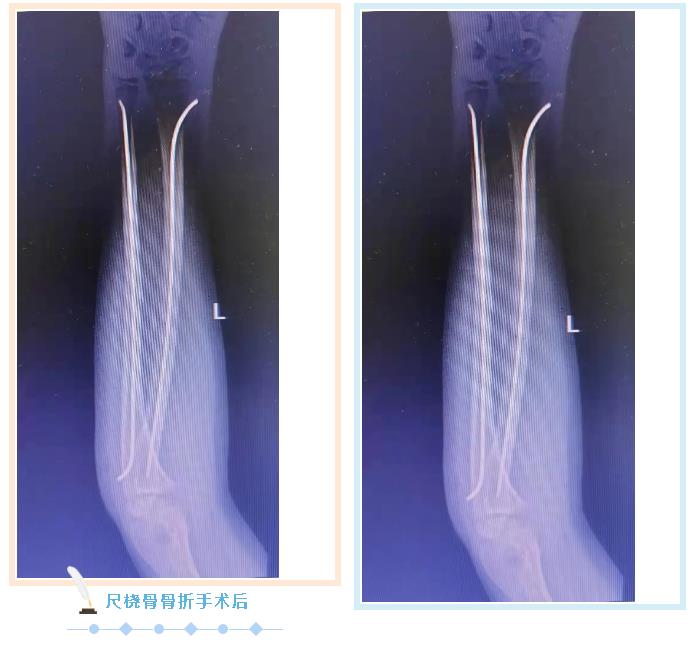

张永青介绍,“弹性髓内钉技术”是儿童骨科界的一次革命,被誉为上帝赐予长骨骨折儿童的礼物,该项技术可在保护骺板不受损伤的前提下,利用多点固定的原理,微创、有效地治疗4-12岁的四肢骨折患儿,该技术利用钛合金或不锈钢良好的弹性、恢复力将作用于长骨的3个接触点转换成推力和压力,从而使骨折复位,有足够的力量抵抗骨折端移位作用,该方法不需要剥离骨膜和切开骨折端,不干扰骨骺生长,也不破坏骨折端血运,弹性固定、局部微动、创伤小、骨折愈合快,术后3周即可进行功能锻炼,术后1个月功能恢复正常。

887700线路检测网骨伤科自2018年在我市率先开展弹性髓内钉技术至今,共收治20多例四肢长骨骨折患儿,手术均为闭合复位或小切口辅助复位,在40分钟内完成,创伤小,恢复快,术后3-5天即可出院,大大减少了治疗费用和住院时间,减少了患儿的痛苦。